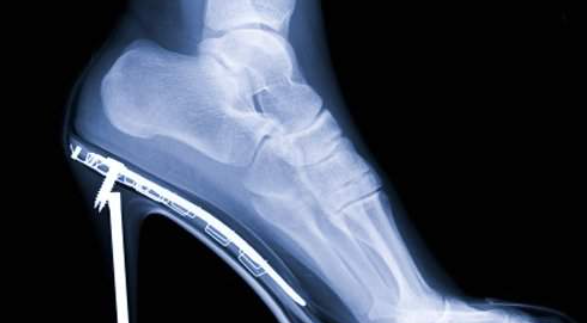

그리고 정확하게는 발바닥 아치 모양에 생긴 것이라고 하며 이 부위를 족저 근막이라 하며 발뒤꿈치와 발가락 뼈를 이어주는 역할을 합니다.

정상적인 사람의 발에는 28개의 뼈, 33개의 관절, 100개 이상의 근육, 힘줄과 인대가 있습니다.

족저근막은 발의 아치를 지지하는 역할을 하고 걷거나 운동을 할 때 충격을 흡수합니다. 발뒤꿈치에서 발가락까지 뻗어 있는 인대인 발바닥 근막에 생긴 염증으로 정말 극심한 통증이 나타나는 특징있습니다.

- 평소 운동화가 아닌 구두,여성 힐과 같은 불편하고 딱딱한 신발을 자주 착용한 경우